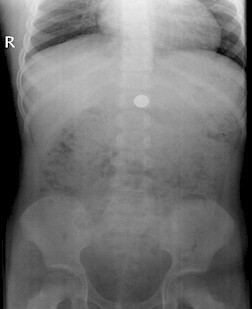

Fallbeispiel - "Low Dose-Aufnahme"

Fremdkörpersuche beim Kind

Beim Spielen Metallkugel verschluckt.

Low Dose Aufnahme zur Lokalisation einer verschluckten Metallkugel.

Fallbeispiel:

Patient: 6-jähriges Kind (weiblich)

Anamnese: Beim Spielen Metallkugel verschluckt! - Ereignis liegt etwa drei Stunden zurück!

Fragestellung: Lokalisation des Fremdkörpers

Durchführung: Abdomen pa im Stehen. (Geht natürlich auch im Liegen). Fragestellungsabhängige digitale Low-Dose-Aufnahme.

Die Aufnahmeparameter: (mit Fuji CR Speicherfolie)

- Raster: nein

- Zusatzfilter: 1 mm Al + 0,2 mm Cu

- Spannung: 100 kV

- mAs-Produkt: 0,5 mAs

Dosis-Flächen-Produkt: 1,15 µGym²

Kritische Anmerkung: Hätte man hier eventuell auch ganz auf die Bildgebung mittels Röntgen verzichten können!?!?